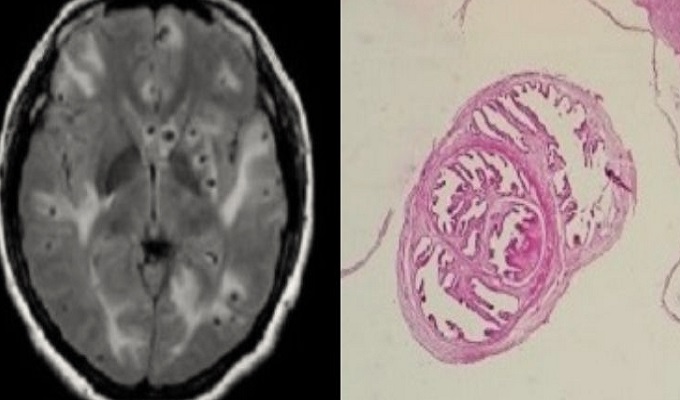

Un caso médico inusual se registró en Estados Unidos: un hombre de 52 años desarrolló gusanos en su cerebro debido a una infección causada por el consumo de tocino crudo. El paciente, quien presentaba migrañas recurrentes que no respondían a tratamientos convencionales, fue diagnosticado con neurocisticercosis, una enfermedad provocada por larvas del parásito Taenia solium.

Tras someterlo a una tomografía y una resonancia magnética, los especialistas confirmaron la presencia de múltiples quistes en las regiones frontal y media del cerebro.

“La neuroimagen y la serología confirmaron el diagnóstico de neurocisticercosis. Fue tratado con medicamentos antiparasitarios y antiinflamatorios”, detallaron los médicos en un artículo publicado en el American Journal of Case Reports.